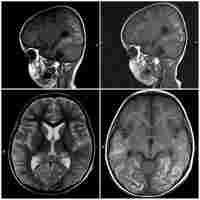

| Abstract | Vertical transmission of SARS-CoV-2 from mother to fetus is widely accepted. Whereas most infected neonates present with mild symptoms or are asymptomatic, respiratory distress syndrome (RDS) and abnormal lung images are significantly more frequent in COVID-19 positive neonates than in non-infected newborns. Fatality is rare and discordant meta-analyses of case reports and series relating perinatal maternal COVID-19 status to neonatal disease severity complicate their extrapolation as prognostic indicators. A larger database of detailed case reports from more extreme cases will be required to establish therapeutic guidelines and allow informed decision making. Here we report an unusual case of a 28 weeks' gestation infant with perinatally acquired SARS-CoV-2, who developed severe protracted respiratory failure. Despite intensive care from birth with first line anti-viral and anti-inflammatory therapy, respiratory failure persisted, and death ensued at 5 months. Lung histopathology showed severe diffuse bronchopneumonia, and heart and lung immunohistochemistry confirmed macrophage infiltration, platelet activation and neutrophil extracellular trap formation consistent with late multisystem inflammation. To our knowledge, this is the first report of SARS CoV-2 pulmonary hyperinflammation in a preterm newborn with fatal outcome. |